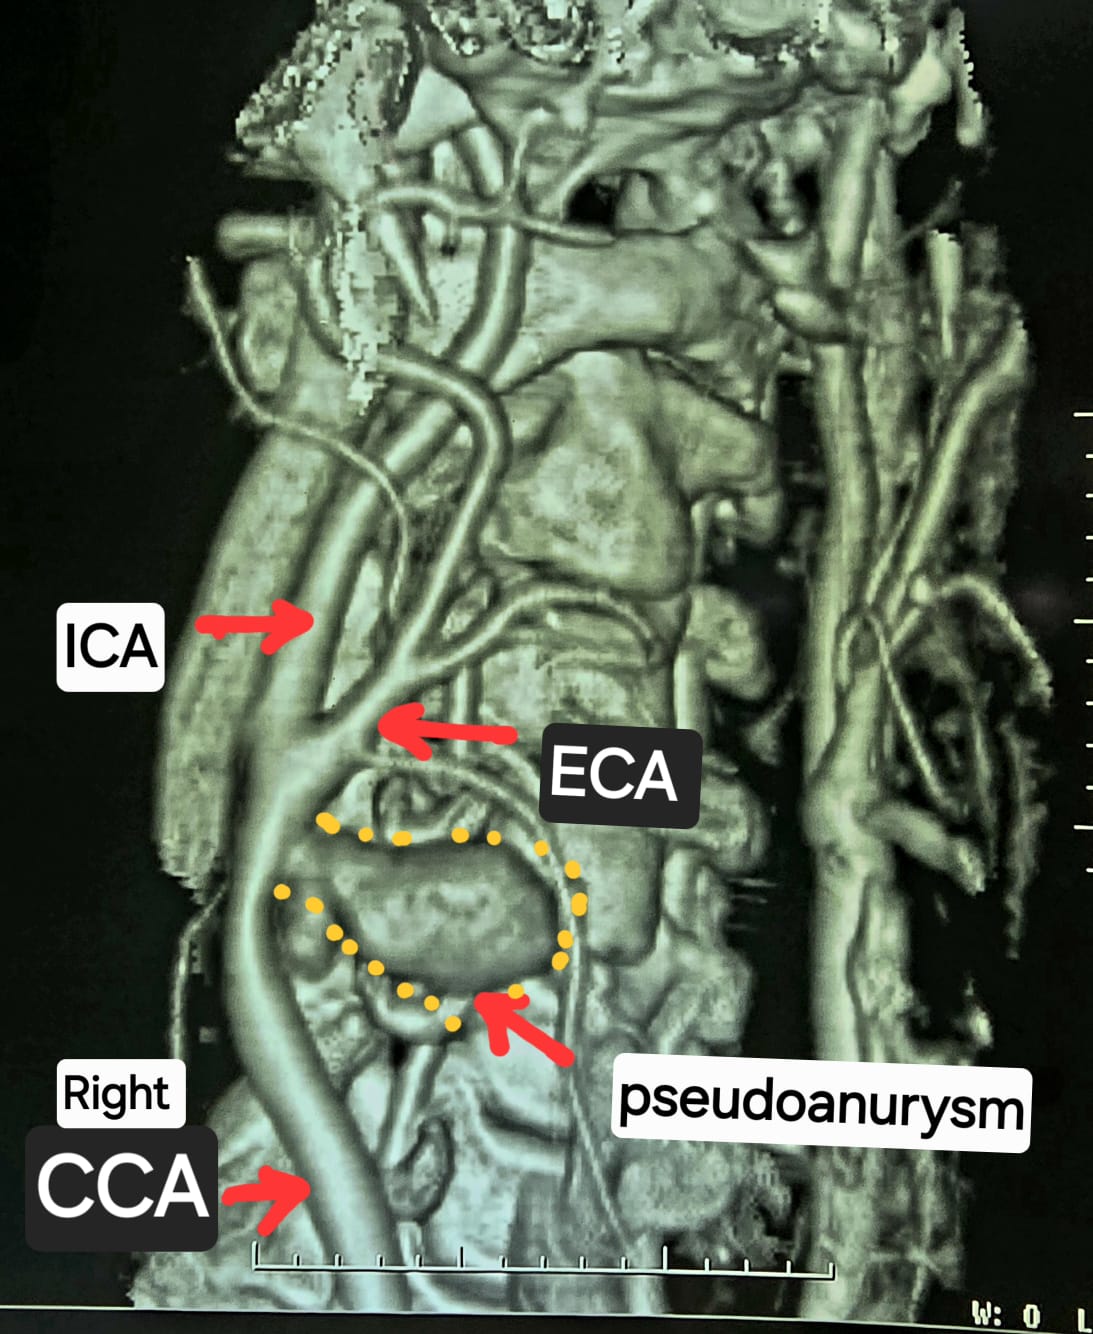

सीटी एंजियोग्राफी से हुआ दुर्लभ रोग का खुलासा

गर्दन की सीटी एंजियोग्राफी जांच में यह चौंकाने वाला तथ्य सामने आया कि मरीज की दाईं कैरोटिड आर्टरी स्वतः फट चुकी है और आसपास कैरोटिड आर्टरी स्यूडोएन्युरिज्म बन गया है। स्थिति अत्यंत नाजुक थी, इसलिए मरीज को तुरंत हार्ट, चेस्ट एवं वैस्कुलर सर्जरी विभाग में स्थानांतरित किया गया।